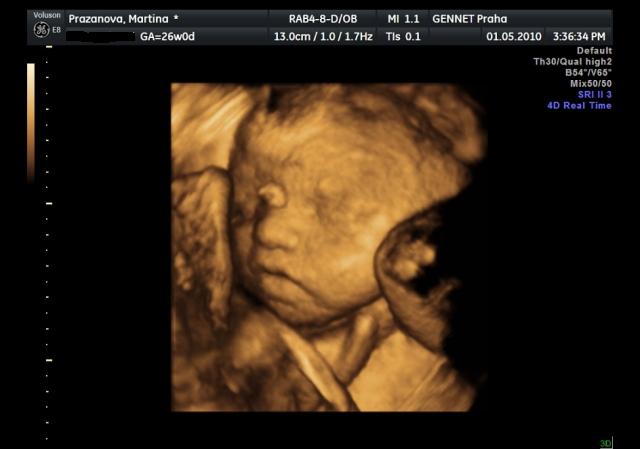

Už se nemůžeme dočkat 1.5....jdeme na 4D UTZ, tak doufám, že se nám ten náš klučík ukáže v plné své kráse 🙂))